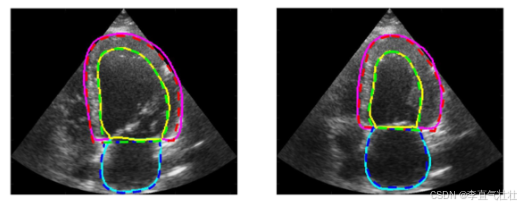

HMC-QU

该数据集包括在 2018 年和 2019 年期间获得的 162 个心尖 4 腔 (A4C) 视图二维超声心动图 (echo) 记录的集合.用于检测心脏左心室 (LV) 壁上的心肌梗塞(心脏病发作). 视频来自一年内执行的 10, 000 多个检查, 其中包括 800 多例因急性 ST 段抬高心肌梗死 (MI) 入院的病例. HMC-QU 数据集中包含的回声属于 93 名 MI 患者(均为首次和急性 MI)和 69 名正常(非 MI)受试者

链接: link